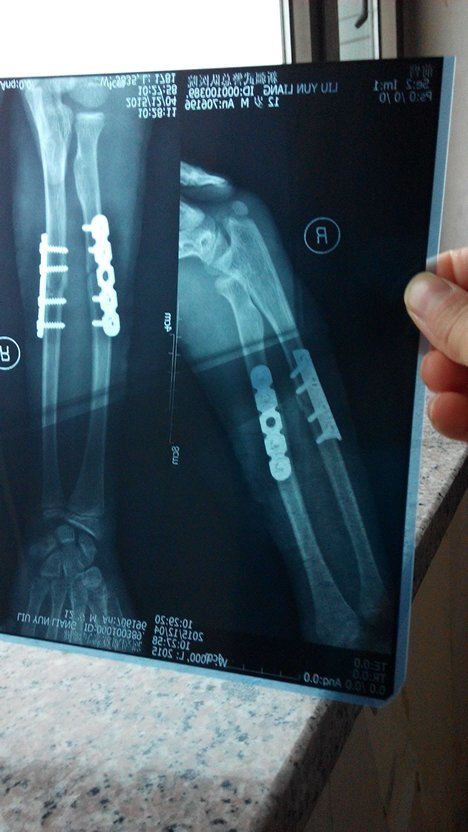

孩子在学校走廊被同学绊到骨折并做手术 对方应怎样赔偿